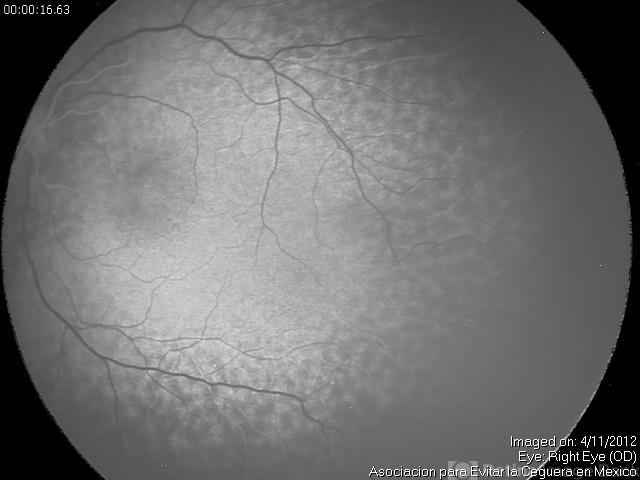

- retinopathy of prematurity (ROP), choriocapillaris

- Maria A. Martinez-Castellanos. Asociacion para Evitar la Ceguera en Mexico

- Imaging device

Fundus camera

RetCam II - Description

- Lobular choroidal filling in a baby with stage 1 ROP, the macular area has a different filling pattern that the rest of the retina.